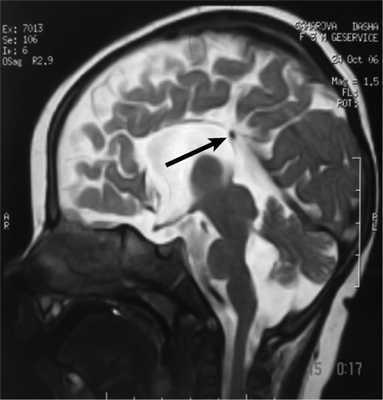

Рис. 2. Результаты обследования больной С., 8 лет. а, б, в — МРТ головного мозга (сагиттальная и аксиальная проекции): сочетание АМТ и диффузной пахигирии (стрелки).

Рис. 3. МРТ головного мозга (сагиттальная проекция) больной С., 7 лет. АМТ (стрелка).